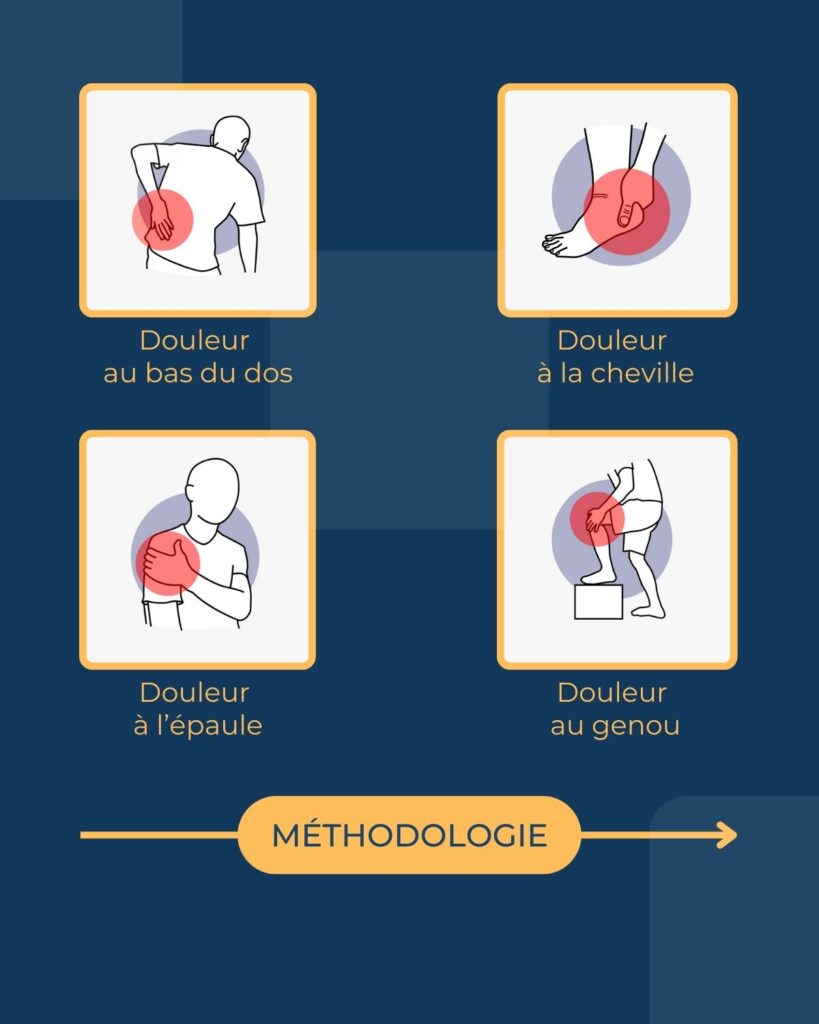

Accès aux soins de réadaptation : programmes de groupe versus interventions individuelles

Les programmes d’exercices supervisés en groupe sont-ils aussi efficaces que les interventions individuelles habituelles en physiothérapie ?

Accès aux soins de réadaptation : programmes de groupe versus interventions individuelles